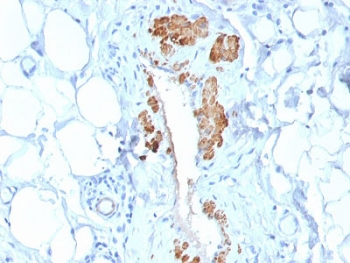

IHC: Formalin-fixed, paraffin-embedded human Leiomyosarcoma stained with SMMHC antibody (MYH11/923).